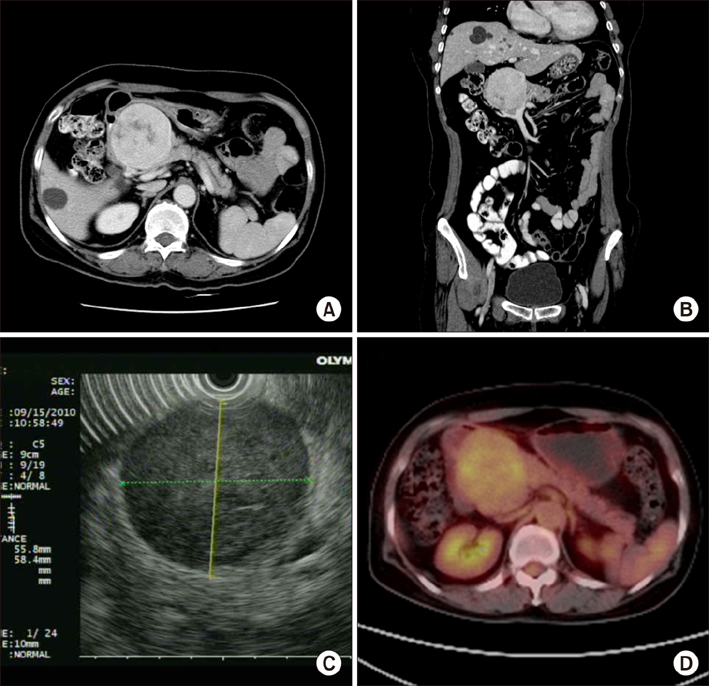

- Gastrointestinal tumors (GISTs) of the pancreas are extremely rare with limited individual case reports and small number of case series. Herein, we report a case of pancreatic extragastrointestinal stromal tumor (EGIST) along with literature review. A 64-year-old female patient was referred to us for treatment of an abdominal mass detected by ultrasonographic examination. The tumor was located in the periamullary region. Under a preoperative diagnosis of a duodenal GIST, we performed a pylorus preserving pancreatoduodenectomy for this lesion. Laboratory examination results were within normal ranges. On pathologic gross examination, the tumor measured at 7 cm in its greatest dimension almost entirely involved the pancreatic head. Its cut surface was rubbery and white. It was surrounded by a thin pseudocapsule and well demarcated. Histopathological examination of the specimen showed a cellular lesion with compressed pancreatic tissue at peripheral. Mitotic count was 5 per 50 high-power fields. Immunohistochemically, neoplastic cells were positive for antibodies against C-KIT (CD117), CD 34, and vimentin. However, smooth-muscle actin reactions with antibodies against S-100 or desmin were negative. Based on above findings, the tumor was finally diagnosed as GISTs originating from the pancreas. The patient has been followed up postoperatively for 72 months. There is no evidence of recurrence. Here we report this case of pancreatic EGIST presenting as a solid neoplasm along with literature review of cases previously described. Our review on pancreatic EGISTs is limited and insufficient to make a conclusion regarding its clinical features. Those manifested large masses tended to have an aggressive biological and clinical behavior. Thus, pancreatic EGISTs need to be carefully differentiated. Adequate surgical intervention is necessary for pancreatic EGISTs.